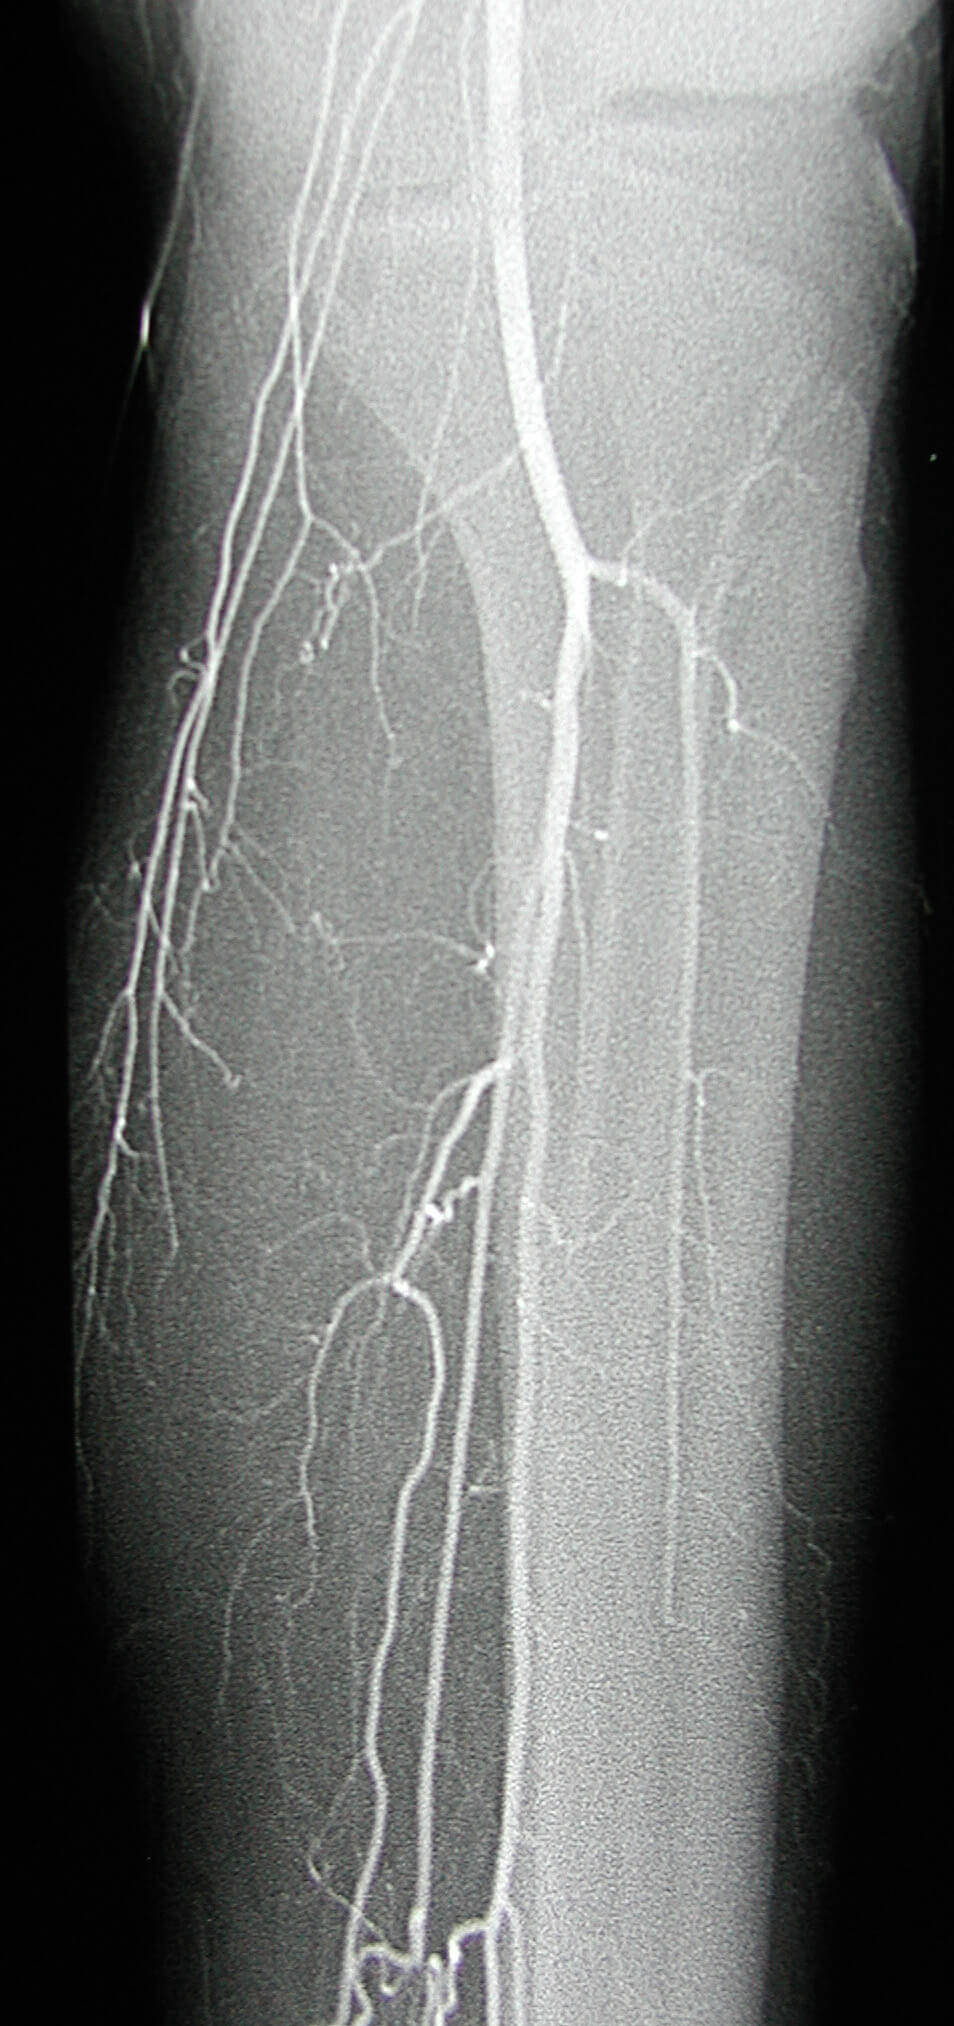

Image from a LLE angiogram demonstrating occlusion of the anterior tibial, posterior tibial, and peroneal arteries at the mid-calf with corkscrew collateral vessels from the mid-calf to the foot.